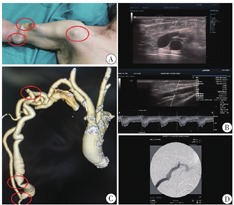

患者女,76岁,因"原发性肾小球肾炎;慢性肾脏病5期"于2011年接受以右颈内静脉临时导管为血管通路的血液透析,同时行右前臂自体动静脉内瘘建立术,术后6周过渡至内瘘穿刺进行血液透析,每周3次。2015年因右前臂内瘘闭塞,行右前臂移植物动静脉内瘘建立术。2016年因右前臂移植物内瘘血栓形成,行右上肢高位内瘘(肱动脉-头静脉内瘘)建立术。2020年3月出现透析中静脉压升高(250 mmHg),拔针后压迫时间延长。查体发现上臂头静脉走行迂曲、打折,伴瘤样扩张,肩部可见头静脉弓走行迂曲。自吻合口起,沿头静脉走行区域均可扪及搏动,伴震颤减弱,头静脉弓区域可触及震颤增强,见图1A。超声二维成像结果显示头静脉弓迂曲狭窄,多普勒血流测定肱动脉血流量1 157.5 ml/min,阻力指数0.54,见图1B。内瘘血管增强CT(三维重建)结果显示内瘘吻合口扩张,上臂头静脉迂曲、打折,伴瘤样扩张,头静脉弓迂曲伴狭窄,见图1C。穿刺内瘘头静脉行头静脉弓+中心静脉血管造影,发现头静脉弓迂曲伴狭窄(70%),中心静脉未见异常,见图1D。行吻合口头静脉缩窄+头静脉弓重建术。手术步骤如下:(1)肘窝处切开皮肤,游离肱动脉、内瘘吻合口及近吻合口头静脉(吻合口旁、瘤样扩张处、打折处)区域,头静脉瘤样扩张处应用6-0 Prolene塑形,近吻合口头静脉应用6-0 Prolene行局部缩窄,长度约1 cm,切除局部多余皮肤后,缝合皮肤;(2)锁骨下中外1/3处切开皮肤,游离头静脉弓区域,切除狭窄迂曲部分,两残端用7-0 Prolene行端端吻合,局部止血后缝合皮肤,见图2。术后查体上臂头静脉血管张力较术前明显降低,透析穿刺顺利,透析中静脉压明显下降(180 mmHg)。术后1个月后随访,彩色多普勒超声检查示肱动脉血流量1 088.0 ml/min,阻力指数0.45。术后3个月后随访,肱动脉血流量927.4 ml/min,阻力指数0.46。

注:A:查体改变;B:内瘘血管超声改变;C:内瘘血管增强CT(三维重建);D:内瘘头静脉行头静脉弓+中心静脉血管造影